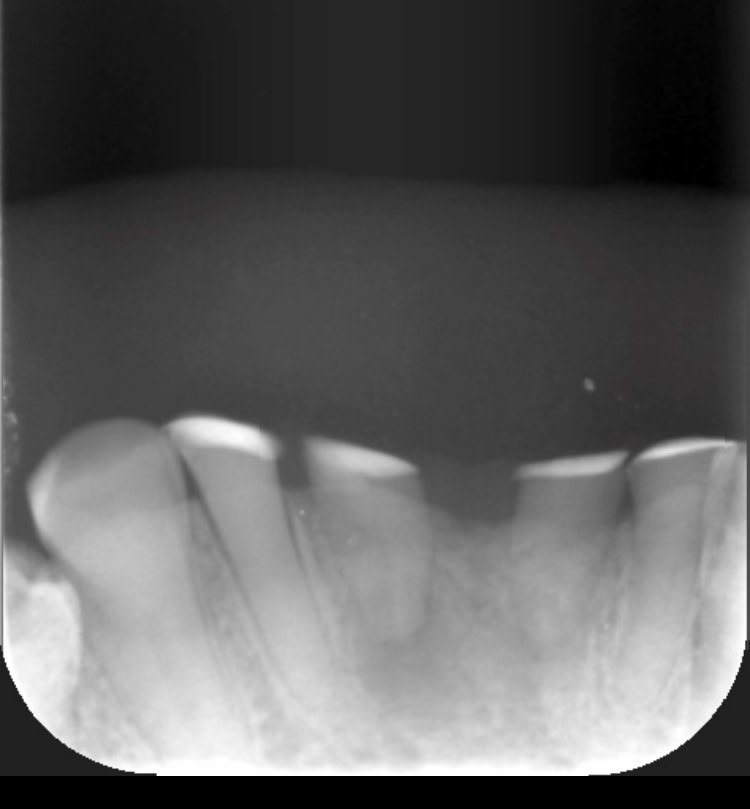

Radio 11